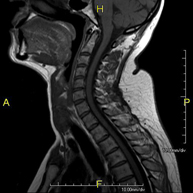

- Cervical spine MRI

This non-invasive diagnostic procedure uses an electromagnetic field and radio waves (from a transmitter and receiver) to acquire high-definition anatomical images of the cervical spine. It is a radiation-free procedure. Indicated for: trauma, spinal degeneration, hernias.

- Thoracic spine MRI

This non-invasive diagnostic procedure uses an electromagnetic field and radio waves (from a transmitter and receiver) to acquire high-definition anatomical images of the thoracic spine. It is a radiation-free procedure. Indicated for: trauma, degenerative problems, hernias, tumours.